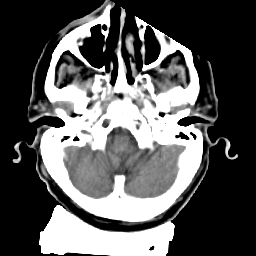

Meningioma: Roentgen-ray CT #2 -- Slice #2

[Home][Help][Clinical] Slice 2